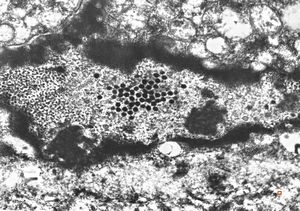

M,50y. | Pneumocystis carinii - lung